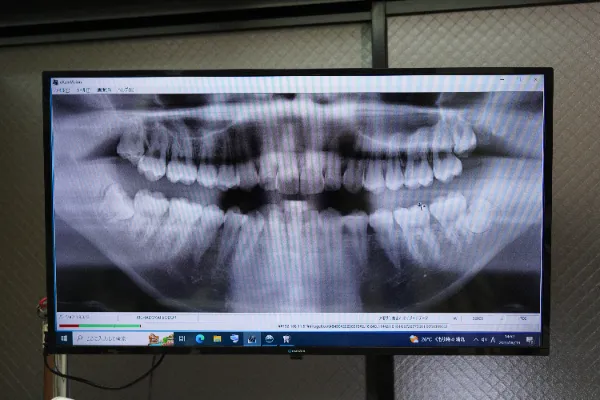

親知らずが神経に近い場合など、症状に応じて歯科用CTを用いた検査を行い、肉眼では見えない部分まで三次元的に確認することで、最適な治療プランを立てていきます。

親知らずの生えている向きは様々です。真っ直ぐに生えているものから、神経近くに埋まっている親知らずもあります。レントゲン検査やCT撮影の結果、長時間の処置が必要と考えられる難症例の場合には、後日のご提案をする場合がございます。(親知らずが完全埋伏、歯の根が複雑、顎骨と接着している状態などが見受けられる場合)